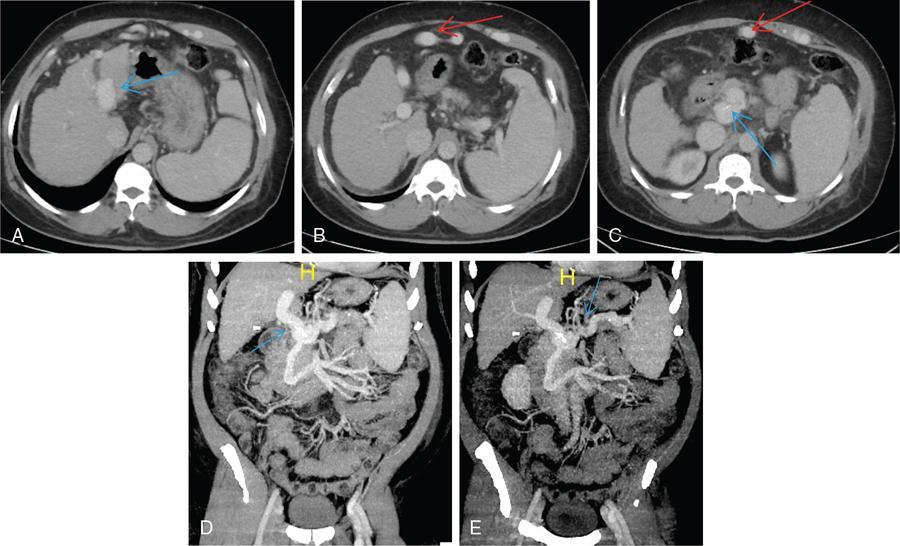

Shrinivas B. Desai, Ritu K. Kashikar, Aman Snehil, Ajay Jhaveri Cirrhosis is a late stage of irreversible scarring of the liver causing abnormality in liver structure and function. Multiple conditions and factors can cause repeated liver damage and scarring ultimately leading to cirrhosis. The most feared complication of liver cirrhosis is the development of hepatocellular carcinoma (HCC). Portal hypertension (PHT) is seen with a variety of conditions but cirrhosis happens to the most important cause. Imaging plays a vital role in noninvasive diagnosis and treatment planning of both cirrhosis and PHT. Liver imaging reporting and data system (LI-RADS) is a standardized reporting system assigning an observation risk of representing HCC. This chapter focuses on discussing aetiologies and imaging of PHT with a lucid review of L1-RADS 2018 version. The portal blood circulation is a unique circulatory circuit as it connects two capillary beds between the liver parenchyma at one end and the gastrointestinal tract and splenic parenchyma at the other end. The portal system ramifies in the liver and ultimately ends in the hepatic sinusoids from where the blood ultimately drains into the inferior vena cava (IVC). The portal vein (PV) originates from the capillary beds in the stomach, intestine and the spleen. The main PV is formed behind the neck of the pancreas by the confluence of the superior mesenteric vein (SMV) and splenic vein. It continues to the porta hepatis where it bifurcates into the left and right branches as it carries nutrient rich but oxygen poor blood to the liver (Fig. 9.9.1). The PV makes up for 75%–80% of the liver’s blood supply while the hepatic artery which arises from the celiac trunk makes up for the remaining 25%. A pathological increase in the portal venous pressure is referred to as PHT. PHT is most often a sequel of chronic parenchymal liver disease and leads to major life-threatening complications due to bleeding from the collateral circulation (most commonly oesophageal varices). Direct measurement of portal pressure (PP) is invasive and often not feasible in most patients and thus imaging plays an important role in the diagnosis of PHT and its complications. The normal portal venous pressure ranges between 5 and 10 mmHg, which is the equivalent of 7–14 cm H2O. The normal hepatic venous pressure gradient (HVPG) is the pressure gradient between the PV and the IVC, is typically 1–5 mmHg. Presence of PHT is indicated by a wedged hepatic venous pressure of more than 5 mmHg. Other definitions include a splenic pressure of more than 15 mmHg or an intraoperative PP of greater than 30 cm H2O. The complications of PHT are seen when HVPG is greater than 10 mmHg and hence this value defines clinically significant PHT. Variceal bleeding is seen with a pressure greater than 12 mmHg. In ideal conditions, the portal circuit is a high flow, low resistance circuit as it has to allow substantial flow rates of 700–1000 mL/min to the hepatic parenchyma from the gastrointestinal tract. Anatomical changes in the organization of the hepatic lobule can result in rise in the portal resistance. These can occur in the form of collagen deposition in the space of Disse, fibrotic scars formed due to regenerative nodule (RN) formation, loss of normal elasticity of the endothelium and distal venous thrombosis. Changes in splanchnic haemodynamics due to factors that increase splanchnic blood flow and increase in intrahepatic vascular resistance due to transformation of stellate cells into myofibroblasts also contribute to the increase in PP gradient. In Western countries, alcoholic cirrhosis and viral cirrhosis are the leading causes of PHT and oesophageal varices. The viral causes form majority of cases leading to cirrhosis and PHT in the Far East and Middle Eastern countries while Schistosomiasis remains an important cause in the African countries. Worldwide, nonalcoholic steatohepatitis (NASH) and hepatitis C are the emerging causes of chronic liver disease (CLD) and PHT. PHT can be classified as cirrhotic and noncirrhotic depending on whether it is associated with cirrhosis or not. This distinction is important as noncirrhotic causes like PV thrombosis are at high risk of development of bleeding but tend to have a better chance of surviving a variceal bleed than a patient with decompensated alcoholic cirrhosis due to preserved hepatic synthetic functions in the former. PHT can also be classified on the basis of the location of the pathology into prehepatic, hepatic and posthepatic causes. Hepatic causes can further be divided into presinusoidal, sinusoidal and postsinusoidal. The causes of portal hypertension have been denoted in Table 9.9.1. The direct measurement of the PP by measuring the HVPG is invasive, expensive not readily available in all patients. Thus, imaging plays an important role in the diagnosis of PHT. Various modalities are used for the imaging diagnosis of PHT. Ultrasonography (USG) and Doppler evaluation have the advantage of being inexpensive, readily available and bedside modality (Table 9.9.2). The role of ultrasound and Doppler in imaging of PHT is to: Grey scale imaging is useful in evaluating the splenoportal anatomy. The evaluation should begin with the liver morphology. Signs of cirrhosis like nodularity of the liver surface with relative atrophy of the right lobe and prominence of the left lobe and caudate should be looked for. Hepatic echotexture appears coarse and more echogenic (Table 9.9.3). Increase in portal venous diameter is a sign of PHT (Fig. 9.9.2). Portal venous diameter of more than 13 or 15 mm has low sensitivity for diagnosing PHT of only 40%–12.5%, respectively. Absolute measurement of the portal diameter as a sign of PHT is also fallacious as in presence of collateral circulation or hepatofugal flow; there may actually be a decrease in the PV diameter. Therefore, a more accurate sign is respiratory variation of PV diameter. An increase in PV diameter of less than 20% with deep inspiration has been reported to indicate PHT with a sensitivity of 80% and specificity of 100%. This has been reported to be an accurate indicator of cirrhosis. Hepatic vein straightness, uniformity of vein wall echogenicity and visualization of at least 1 cm segment of the hepatic vein are the parameters used for evaluation. Splenomegaly is defined as bipolar splenic diameter of greater than 12 cm or largest splenic cross-sectional area passing through the hilum of greater than 45 cm2, and occurs secondary to PHT (Fig. 9.9.3). A total of 65%–80% patients with cirrhosis have splenomegaly on ultrasound. Patients with cirrhosis due to viral hepatitis and primary biliary cirrhosis show splenomegaly more frequently than those with alcoholic cirrhosis. This is an accurate sign of PHT. USG is extremely sensitive with respect to detecting subclinical ascites. Perihepatic space is the most usual site of visualization of minimal ascites. In normal subjects, this ratio is approximately 0.07 and a value above 0.1 suggests the diagnosis of PHT with a 95% sensitivity and specificity. The normal spectral waveform of the hepatic artery is a low resistance flow pattern with forward flow in diastole and a resistivity index in the range of 0.5–0.7. In PHT, the resistivity index of the hepatic artery increases with high resistance flow pattern due to increased peripheral vascular resistance. Resistance index (RI) > 0.78 in the intrahepatic branches of the hepatic artery has been reported to have a sensitivity of 50% and a specificity of 100% for the detection of PHT (Fig. 9.9.11). Pulsatility index (PI) > 1.05 suggests severe PHT with a sensitivity of 86% and specificity of 88% (Fig. 9.9.11). Patency of hepatic veins should be evaluated to rule out Budd–Chiari syndrome as a cause of PHT. The normal hepatic venous waveform (HVW) reflects right atrial activity and this results in a triphasic waveform with one positive and two negative waves. In PHT, this waveform becomes monophasic or biphasic. A monophasic HVW has a sensitivity and specificity of 74% and 95%, respectively, in the diagnosis of severe PHT (Fig. 9.9.12). Dilatation of the splanchnic veins – the SMV and the splenic vein – more than 11 mm are suggestive of PHT with a sensitivity and specificity of 72% and 100%, respectively. A reduction in the respiratory variation of the splenic vein and SMV to less than 40% had a sensitivity and specificity of 79.7% and 100%, respectively, for the diagnosis of PHT (Fig. 9.9.13). The splenic artery reveals an increase in the resistivity index and an RI of >0.63 and a PI of >1 have a sensitivity and specificity of 84.6% and 70.4% for the diagnosis of PHT. Presence of portosystemic collaterals like patent paraumbilical vein, dilated left gastric and short gastric veins are 100% specific sign for PHT (Figs. 9.9.14–9.9.16). Recanalization of the paraumbilical vein, known as the Cruveilhier–Baumgarten syndrome is observed in 43% of patients with PHT, and this is the easiest collateral to assess during the US examination. Various portosystemic collaterals that occur in PHT have been discussed in details in subsection on CT findings in PHT. No Doppler parameter is considered reliable enough to measure PP with sufficient accuracy for use in clinical practice. Oesophageal varices are often present in patients with portosystemic collaterals. Appearance or increase in number of collaterals along with splenomegaly has a high association with variceal formation and growth. USG helps in diagnosis of prehepatic causes like portal stenosis or thrombosis by demonstrating the patency and morphology of the splenoportal system. Arteriovenous fistulae and tumours causing vascular thrombosis as aetiology can be readily detected. USG helps in diagnosis of features of cirrhosis and thus helps differentiate noncirrhotic causes of PHT. USG allows diagnosis of fatty liver disease, which is an emerging cause of cirrhosis. Among the posthepatic causes, USG aids in establishing the diagnosis of Budd–Chiari syndrome by demonstrating the patency and morphology of the IVC and hepatic veins. Owing to the inability of CT to detect flow direction, portal flow rates or pressure gradients, CT is not the primary modality in diagnosis of PHT. Similar to USG dilatation of portosystemic system is a feature of PHT (Fig. 9.9.17). Changes in cirrhosis if present can be seen in the form of surface nodularity, nodules and fibrous septae. CT plays an important role in diagnosis of portal venous thrombosis and evaluating its extent. An acute thrombus is seen as a hypodense filling defect in the vessel causing distension of the venous lumen. Surrounding fat stranding can be seen. A chronic thrombus appears as an eccentric filling defect usually along the wall and is often associated with decrease in vessel diameter. Calcification may be seen in chronic thrombi. Multidetector computed tomography (MDCT) is a useful tool to evaluate portosystemic collateral circulation and recognize complications of PHT. 3D angiography can help understand portal venous and complex variceal anatomy and plan treatment. The various portosystemic collaterals are discussed below. They can be classified into those draining into superior vena cava (SVC) and those draining into the IVC. Magnetic resonance imaging (MRI) is a noninvasive modality used in the evaluation of PHT without the use of ionising radiation. It provides evaluation of parenchymal abnormalities, collaterals and characterization of tumours (Fig. 9.9.28). Spin echo sequences allow characterization of liver masses and liver parenchyma. Loss of flow void allows for detection of thrombosis. Time-of-flight (TOF) angiography is useful in assessing the portal venous system and allows for successful detection of PV thrombosis. The disadvantages of TOF are motion artefacts caused by breathing, long acquisition times and incomplete coverage of the portal venous system. Novel imaging techniques include phase contrast, T1 mapping and magnetic resonance elastography (MRE). The advantage of phase contrast over TOF imaging is that phase contrast imaging acquires information regarding the flow direction in addition to the information regarding the flow velocity. On-phase contrast images signal within vessel is hyperintense when flow is cranial and hypointense when flow is caudal. Look-Locker imaging technique using gradient echo (GRE) MRI sequences with inversion recovery pulse is used to quantify fibrosis by measuring precontrast T1 relaxation times. Interventions in PHT can be aimed at diagnosis or more commonly at management of complications of PHT. HVPG measurement, which is the gold standard for the diagnosis of PHT, can be achieved through cannulation of the PV. Transjugular hepatic biopsy is another diagnostic invasive technique that also allows indirect measurement of PP. Disadvantages include deterioration of hepatic function caused by diversion of portal venous blood flow and shunt dysfunction. TIPSS is contraindicated in patients with congestive heart failure, severe pulmonary hypertension, severe tricuspid regurgitation and hepatic failure. In this technique, a catheter is advanced from the femoral vein into the outlet of the gastrorenal, usually in the region of the left renal vein. The shunt is then occluded with a balloon and sclerosant is injected retrograde to occlude the gastric varices. Histological development of RNs surrounded by fibrous septae in response to chronic liver injury, progressing PHT and end-stage liver disease is termed as cirrhosis. Although initially considered an end-stage phenomenon in CLD, recent evidence suggests that the histological fibrosis can be reversible in early stages with the initiation of specific therapies, for example, in viral cirrhosis with the initiation of antiviral therapy. The one-year mortality rate in cirrhosis varies widely from 1% to 57% depending on the occurrence of complications. Cirrhosis can have a wide variety of causes ranging from congenital to acquired and infectious to noninfectious. It is also a major aetiologic risk factor for the development of HCC. Imaging plays an important role in aetiologic diagnosis of this diverse entity as well as in the diagnosis and management of its complication and surveillance for oncological transformation.